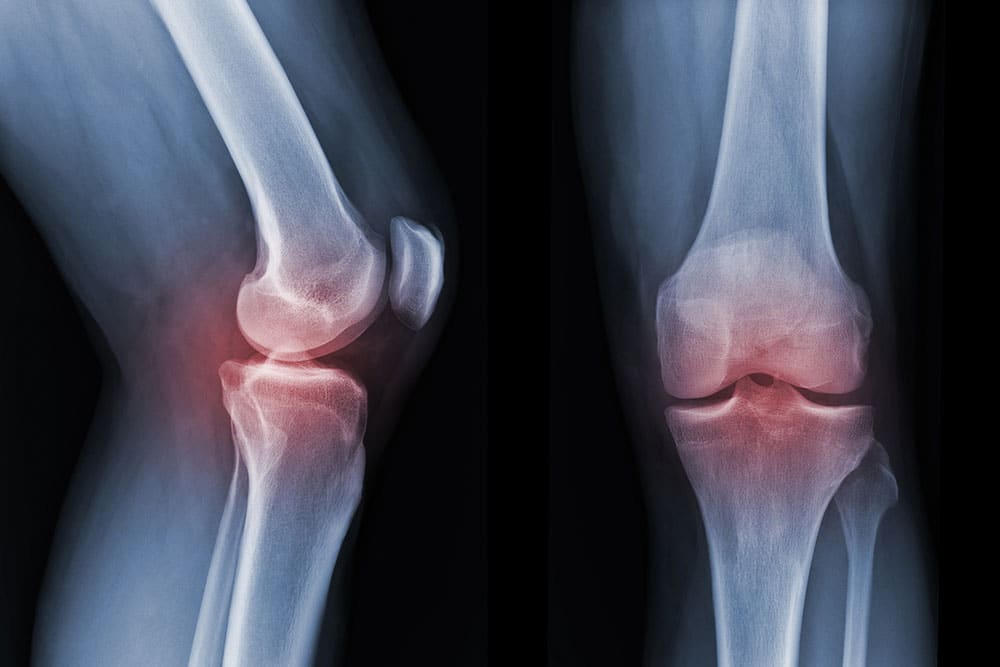

Since partial knee replacement is designed for wear that’s limited to one compartment of the knee, suitability depends on where the damage is concentrated, and whether the rest of the joint still functions well. It’s most often considered when changes are confined to a single tibiofemoral compartment, either the medial (inner) or lateral (outer) side of the knee, with preserved stability and alignment. In comparison, it’s generally not advisable when damage affects more than one compartment, or when significant ligament instability is present. Situations where partial knee replacement is considered include:

Partial knee replacement is usually assessed based on three things: where the damage sits, how the knee behaves under load, and whether the rest of the joint is still healthy enough to preserve. In general, it’s most suitable when wear is confined to one compartment, while stability and movement remain well controlled. This type of knee surgery is typically considered when: